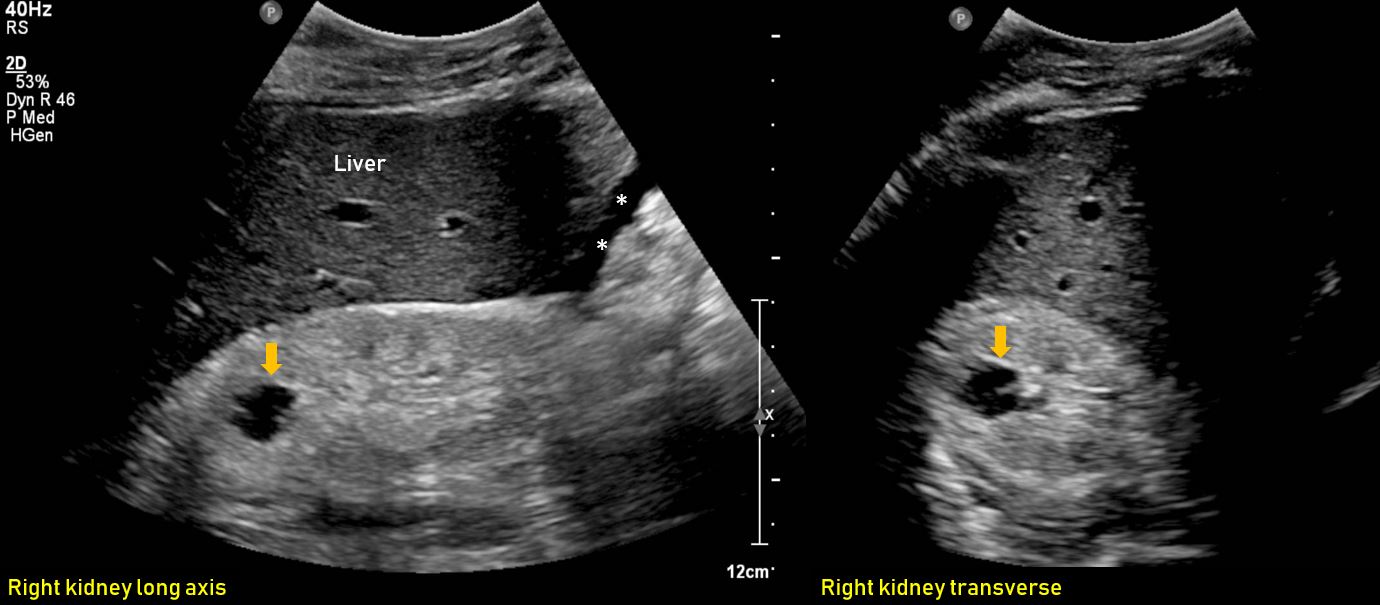

Ultrasound features of Kidney Cysts Renal Fellow Network Types Of Cysts Ultrasound Ultrasound assessment of the morphological and vascular features of a mass has been shown to be highly effective for. A tumour is an unusual area of extra tissue. Understanding the type of ovarian cyst present is critical in. A pelvic ultrasound can detect cysts as well as aid in categorizing cysts by type, size, shape, and location. Some types of. Types Of Cysts Ultrasound.

Ultrasound features of Kidney Cysts Renal Fellow Network Types Of Cysts Ultrasound Ultrasound assessment of the morphological and vascular features of a mass has been shown to be highly effective for. A pelvic ultrasound can detect cysts as well as aid in categorizing cysts by type, size, shape, and location. Understanding the type of ovarian cyst present is critical in. A cyst is a small sac filled with air, fluid, or other. Types Of Cysts Ultrasound.

Ultrasound features of Kidney Cysts Renal Fellow Network Types Of Cysts Ultrasound The most common types of lumps are cysts and tumours. Understanding the type of ovarian cyst present is critical in. A tumour is an unusual area of extra tissue. Some types of cyst are entirely normal: The images show two normal ovaries with several anechoic, simple cysts. Ultrasound assessment of the morphological and vascular features of a mass has been. Types Of Cysts Ultrasound.

Ultrasound features of Kidney Cysts Renal Fellow Network Types Of Cysts Ultrasound Some types of cyst are entirely normal: A pelvic ultrasound can detect cysts as well as aid in categorizing cysts by type, size, shape, and location. The images show two normal ovaries with several anechoic, simple cysts. A tumour is an unusual area of extra tissue. The most common types of lumps are cysts and tumours. A cyst is a. Types Of Cysts Ultrasound.

Ultrasound features of Kidney Cysts Renal Fellow Network Types Of Cysts Ultrasound A tumour is an unusual area of extra tissue. A cyst is a small sac filled with air, fluid, or other material. The most common types of lumps are cysts and tumours. The images show two normal ovaries with several anechoic, simple cysts. Some types of cyst are entirely normal: A pelvic ultrasound can detect cysts as well as aid. Types Of Cysts Ultrasound.